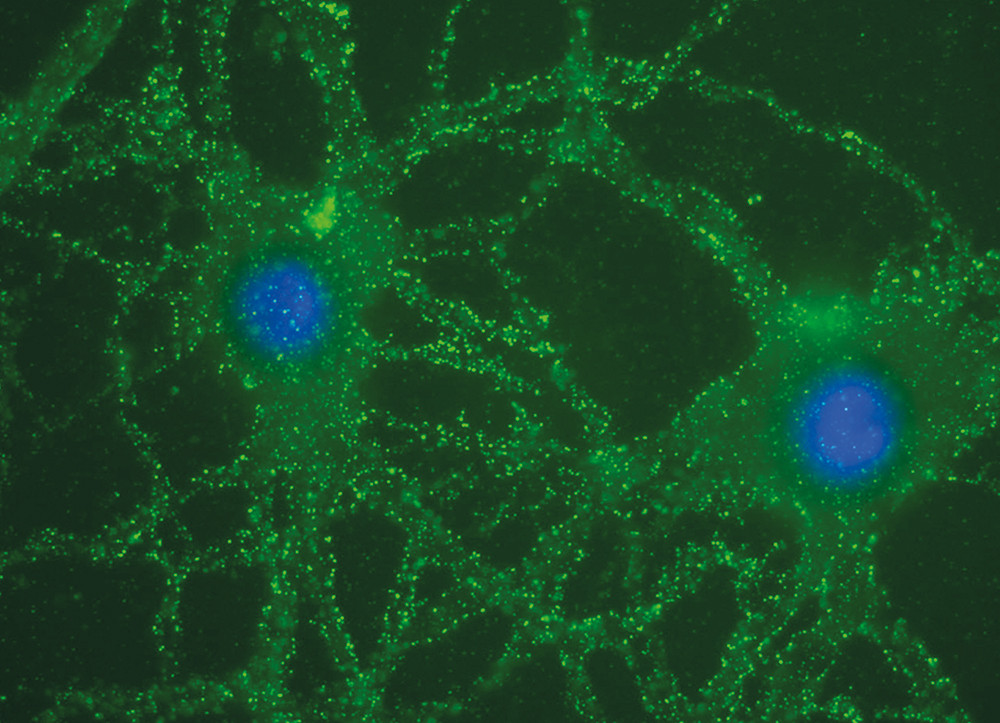

Den tydelige effekten av plasmautskiftning pekte klart i retning av en immunmediert sykdom, men spesifikke antistoffer eller andre immunologiske markører kunne ikke påvises under sykehusoppholdet. Før behandling med plasmautskiftning ble spinalvæske og serum fra pasienten fryst ned. I lys av rapport om en ny type autoimmun encefalitt (7), ble det nedfryste prøvematerialet senere sendt til University of Pennsylvania, USA. Analysene viste tilstedeværelse av NMDA (N-metyl D-aspartat)-reseptorantistoffer i serum og spinalvæske (fig 2) (8), og vi konkluderte derfor med at diagnosen var anti-NMDA- reseptorencefalitt.

EEG-mønsteret er nesten alltid patologisk og viser langsom rytme iblandet epileptisk aktivitet (14). Som hos vår pasient (fig 1), kan den endrede rytmen opptre relativt ensidig (15). Patologiske funn i spinalvæsken finnes i flertallet av tilfellene og omfatter moderat økning i antall leukocytter og/eller lett økt totalproteinnivå og av og til oligoklonale bånd (11). MR av sentralnervesystemet viser patologiske endringer hos halvparten av pasientene, og kan ved T2-vektet undersøkelse eller FLAIR (fluid attenuated inversion recovery)-undersøkelse vise beskjeden hyperintensitet i temporallappene, lillehjernen, basalgangliene, hjernestammen og av og til i ryggmargen (11). Diagnosen kan bekreftes ved påvisning av spesifikke NMDA-reseptorantistoffer i spinalvæske og serum. (Prøver analyseres ved Nevro-Revma-laboratorium, Haukeland universitetssykehus, Bergen.) Pasientene bør undersøkes med tanke på underliggende tumor. Forekomst av neoplasme øker hos pasienter over 18 år. Hos kvinner er teratom i ovariet den hyppigst assosierte tumor. Relevante undersøkelser for pasienter som mistenkes for anti-NMDA-encefalitt er oppsummert i ramme 2.